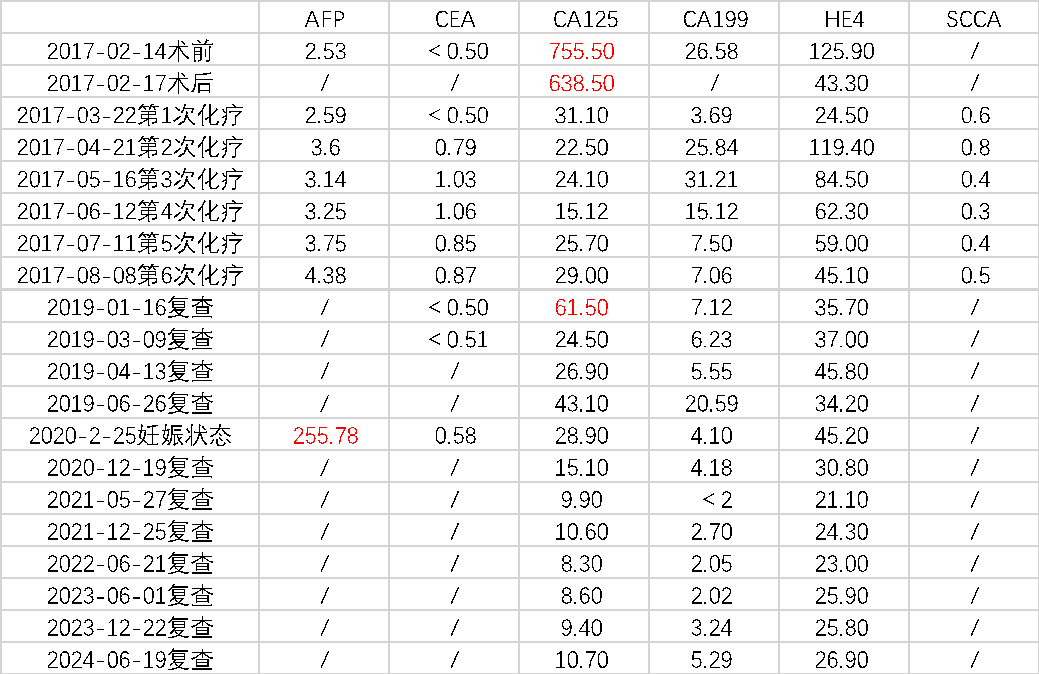

【现病史】 【既往史】 【婚育史】 【月经史】 【家族史】 直系亲属无类似疾病史。父亲高血压病史,否认其他家族遗传性疾病史。 【入院后的检查检验】 ✦经腹部+阴道联合超声(2017-02-15,我院): ✦肿瘤指标: 【入院诊断】 2、子宫颈炎 3、不孕症 中青年女性,已婚未育,因“B超发现盆腔包块半年余”就诊。患者右侧附件区可见一个混合回声,形态不规则,边界尚清晰,内部回声不均匀,大小约98mm*70mm*64mm,其内可见不规则液性回声,附壁可见低回声突起,大小约38mm*15mm*39mm,其内可见点状彩色血流信号可见彩色血流信号。患者既往有卵巢囊肿切除术史。肿瘤指标糖类抗原CA125:755.5U/mL,人附睾蛋白4:124.9pmol/L。 经腹双侧卵巢肿瘤剥除术+大网膜切除+阑尾切除术+腹主动脉旁淋巴结取样术+盆腹腔多点腹膜活检术+盆腹腔转移肿瘤结节切除术 【术中探查见】 【术中快速病理】 【术后常规病理】 【术后基因检测结果】 【术后诊断】 2、卵巢交界性浆液性乳头状瘤Ⅲc期 3、右侧卵巢巧囊术后 4、腹主动脉旁淋巴结内异症 【术后治疗】 TC化疗6L疗程。化疗期间予诺雷德3.6mg皮下注射。 【术后妊娠】 ✦产科病史: 入院检查:宫高:34cm,腹围:104cm,估计胎儿大小:3500g,胎方位RSA,FHR:144次/分,先露:臀。 辅助检查:B超示:双顶径:93mm,腹周径:307mm,股骨长:68mm,羊水指数:89mm,胎盘附着于子宫后壁,Ⅲ-级,考虑胎儿脐带绕颈一周可能,LSA位。 ✦肿瘤指标: ✦MRI(2020-02-25,我院): ✦手术方案: 于2020-02-26在全麻下行子宫下段剖宫产术+次广泛性子宫切除术+双侧附件切除术+盆腔淋巴结清扫术+腹主动脉旁淋巴结清扫术(肾静脉水平)+盆腹腔转移肿瘤结节切除术+盆腹腔多点腹膜活检术+部分网膜切除术 ✦分娩记录: 手托臀娩出一女婴,体重2850克,评分10-10分 ✦术中快速: (左卵巢)交界性浆液性乳头状囊腺瘤,部分呈微乳头型,伴上皮内癌,待常规多取材除外有无浸润。 ✦术后常规: 患者术后每隔半年规律复查至今,复查内容包括肿瘤指标(CA125、CA199、HE4)、生化全套检验及B超检查,均未见明显异常。 延展讨论 1、手术方案的选择 卵巢交界性肿瘤相对于卵巢肿瘤而言恶性程度较低,复发率低且复发较晚,患者生存期延长,死亡率较低。近年来女性卵巢交界性肿瘤的发病年龄趋于年轻化。在临床调研中显示有50%的患者确诊时<40岁。由于BOTs患者多为育龄期女性,对生育功能的保留是治疗过程中应重点考虑的因素之一。目前保留生育功能手术术式有单侧肿瘤剔除术、单侧附件切除术、双侧肿瘤剔除术(BOC)和单侧附件切除术+对侧肿瘤剔除术(UAC),分期不是绝对禁忌证。此外,BOT易复发,常见高危因素有FIGO分期、手术方式和组织学类型等。浆液型、晚期、微乳头和双侧肿瘤与高复发率相关;单侧附件切除术预后总体优于肿瘤剔除类手术。对于强烈要求保留生育功能的患者需要充分评估肿瘤特性、做好术前告知,谨慎选择术式,术后规律随访。 由于卵巢交界性肿瘤一般分化良好,其代谢活性近似于良性肿瘤,缺乏对化疗药物的敏感性或耐药性,故对于早期患者和术后无残留病灶的患者不建议立即进行辅助性化疗,而应积极定期随访。 2、术后辅助生殖技术 研究表明卵巢交界性肿瘤实行保留生育功能手术对后续不孕症行体外受精、胚胎移植的妊娠结局无显著不良影响。BOTs患者实施辅助生殖技术(assisted reproductive technology,ART)的时机十分重要,大部分观点认为应当在术后至少1-2年再尝试ART但考虑到ART治疗的间隔时间过长可能对于女性卵巢储备功能有较高的要求,术后的妊娠应当在评估了肿瘤复发风险和预后的情况下尽快进行,在术后半年至1年内尝试妊娠。而对于术前术后检测卵巢功能出现下降,无或低自然受孕机会的患者应缩短ART的时间间隔。对于术后病理提示肿瘤有微乳头或间质浸润等情况者,应尽早或在术后半年至一年内开始尝试妊娠。 3、妊娠时机的选择 本案例中患者于化疗结束后半年开始积极备孕,行IVF失败后自然受孕,并于腹腔镜双侧卵巢肿瘤剥除术后2年妊娠。对于有生育需求的患者,妊娠时机的选择也十分重要,原则上应避开复发高峰期,可在术后6-12个月内尝试妊娠;术后选择化疗的患者应在停用化疗药物6-12个月后。还应继续关注其卵巢功能及激素水平,在孕早期及时补充黄体酮保胎,以期达到良好的妊娠预后。

甲胎蛋白:2.531μg/L,癌胚抗原<0.50ng/mL,糖类抗原CA125:755.5U/mL,糖类抗原CA199:26.58U/mL,人附睾蛋白4:124.9pmol/L。

糖类抗原CA125:28.90U/mL,甲胎蛋白:255.78μg/L,人附睾蛋白4:45.20pmol/L,癌胚抗原:0.58ng/mL,糖类抗原CA199:4.10U/mL。